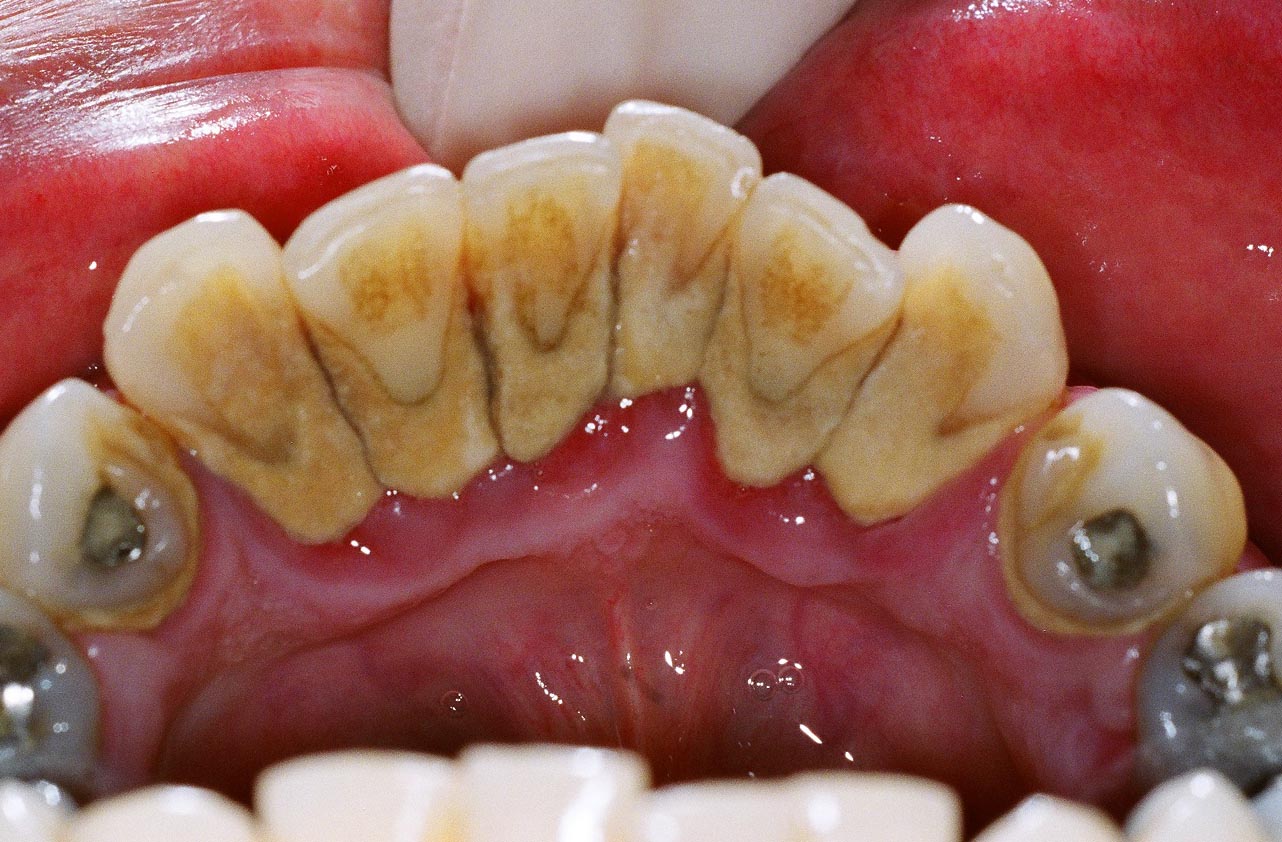

CALCULO DENTAL

El cálculo dental es placa dental calcificada. El sarro o cálculo dental es la causa principal de la inflamación de las encías y la infección periodontal.

Es una película pegajosa y casi invisible formada por las bacterias que habitan en la cavidad oral que se extiende continuamente alrededor de los dientes y de las prótesis dentales que haya en la boca.

El cálculo dental está compuesta por los productos de residuo de las bacterias, unas toxinas que dañan las encías. Las toxinas no sólo afectan la encía, sino también destruyen el hueso subyacente que soporta los dientes provocando la periodontitis.